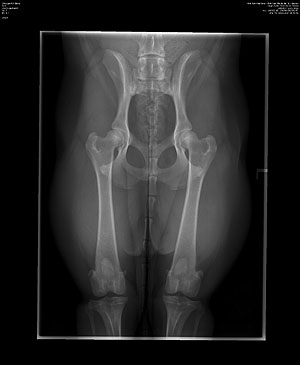

In den vergangenen Tagen erreichten mich 3

HD/ED-Röntgengutachten von Nachkommen meines Rüden

CH Xanthos ex Chelsea: Preston ex Chelsea: HD: A2 / A1,

ED-Grad: 0 / 0 Darwin von Salinamonte: HD: A1 / A1,

ED-Grad: 0 / 0 Dobby von Salinamonte: HD: A1 / A1,

ED-Grad: 0 / 0

HD-Röntgenbild: Preston ex Chelsea

Dobby von Salinamonte